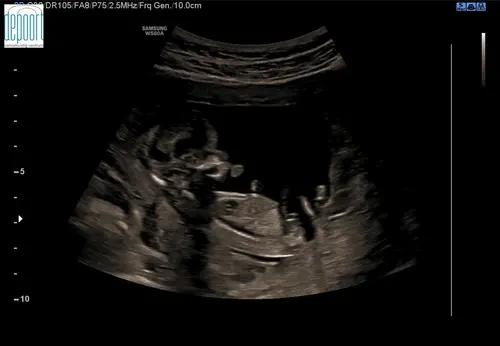

Ziet iemand hier de nub op? Met 13+4 weken

Ik denk een meisje te zien. Wat denk je zelf?🩷